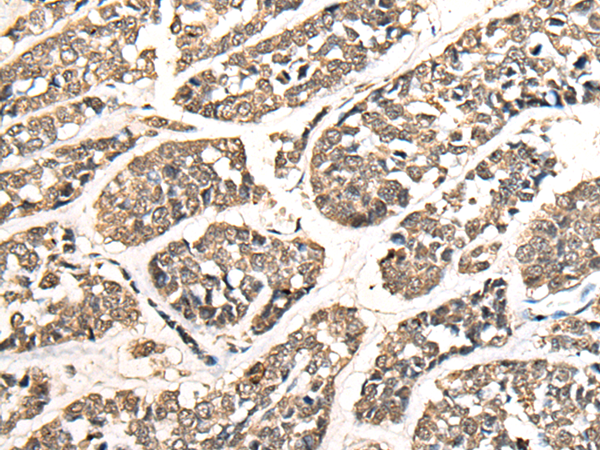

IHC positive control: |

Human esophagus cancer |

IHC Recommend dilution: |

25-100 |